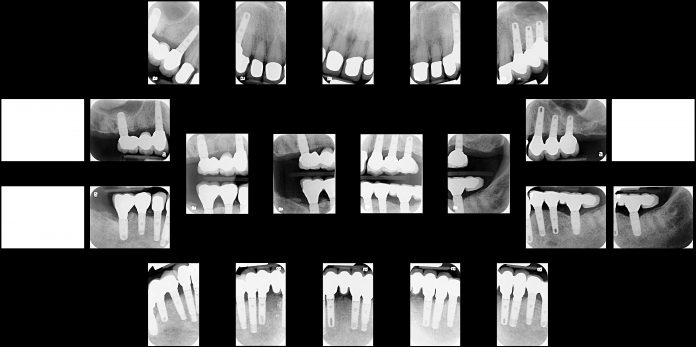

The greater the amount of bone loss, the greater the amount of diagnostic work up that is required to “get it right”. Advancement in dental technology can now aid dental professionals in this diagnostic work and make the examination faster and more precise. Precise planning is possible with a 3D Xray (the CBCT-cone beam-Xray), which provides a great deal of information for planning the implant placements such that they are ideally positioned.These preferred placements increase the jaw’s stability and the long-term success of the implants.

Implants provide additional jaw support, since they are titanium “roots” which are ramparts, or support for the bone. Precise preoperative planning provides the best results, even if a great deal of bone has been lost.